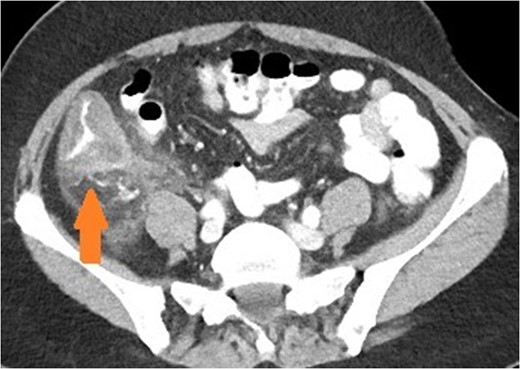

Coronal view of patient with appendicitis. Dilated and thick walled appendix (arrow).

Appendicitis features include a fluid-filled dilation (>6 mm) and thickening of the appendiceal wall with mild-to-moderate peri-appendiceal fat stranding [5]. Peri-caecal inflammation may occur, characterised by segmental eccentric bowel wall thickening centred over the appendiceal orifice. Importantly, the submucosa (expanded and low density), muscularis and serosa (both slightly thickened and enhancing more than normal) may be delineated in a stratified or layered pattern. Other complications may be present such as perforation or abscess formation, which are seen as rim enhancing collections. Rarely, hepatic abscesses may be present as a manifestation of portal pyaemia, characterised by diffuse liver lesions close to the portal vein tributaries.